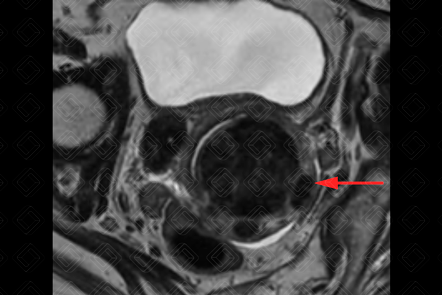

Descrição das figuras 1, 2, 3 e 4: Ressonância magnética da pelve feminina. Imagens pesadas em T2 nos planos axial e sagital (A = bexiga; B = útero; C = reto). Útero em retroversão, de contorno lobulado e sinal heterogêneo, por conta de nódulos miometriais, bem delimitados, hipointensos em T2, compatíveis com leiomiomas, destacando-se:

• Transmural, corporal posterior, medindo 5,0 x 4,8 x 4,6 cm (setas vermelhas à direita);

• Subseroso, corporal lateral direito, medindo 3,0 x 2,0 x 1,8 cm (setas vermelhas à esquerda).